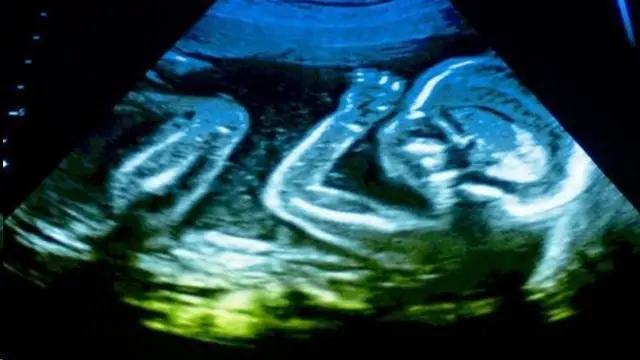

Миграцияда жүргөн кош бойлуу аялдар

Учурда миграцияда жүргөн аялдардын саламаттыгы олуттуу көйгөй бойдон калууда. Би-Би-Си Екатеринбургда иштеген дарыгер Гүлшан Долонбаеваны кепке тартып, мигрант аялдардын көйгөйлөрү тууралуу сурады.

Гүлшан Долонбаева: Мен Екатеринбург шаарындагы №14 мамлекеттик төрөт үйүндө иштейм. Кыргызстандык кыз-келиндер бизге көп кайрылышат. Бирок кыз-келиндер дарыгердин көзөмөлүнөн өтпөй жүрүп, төрөт учурунда өлүмгө дуушар болгондор бар.